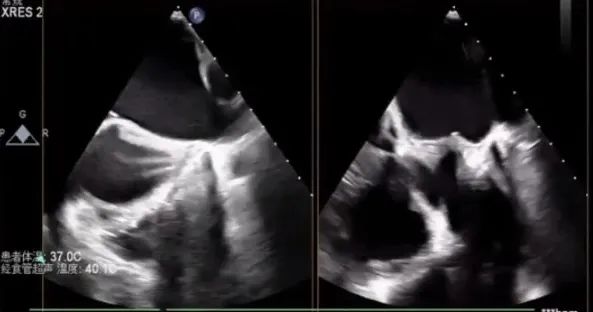

经食道超声检查

经食道检查结果显示,1区瓣叶结构良好,主要脱垂集中于P2区,3区未见明显受累。

进一步评估患者病变情况,前叶长度2.74mm,后叶长度1.93mm;房间隔前后径4.0cm,房间隔长径6.9cm,瓣口面积6.27cm²,平均跨瓣压差5mmHg。

术中观测,卵圆窝范围较小,解剖位置偏下偏前;即便选择其最靠后的位置进行穿刺,穿刺高度仍受限制。

最终穿刺高度受限,仅3.3cm

穿刺位点良好,3点钟

置入CDS并调整位置与方向,操作过程中调整M键向“+”键方向旋转,使大鞘头端指向二尖瓣环,此时尚未完全完成骑跨。术中经TEE观察可见,因左房空间受限、穿刺高度不足,CDS已跨过二尖瓣。